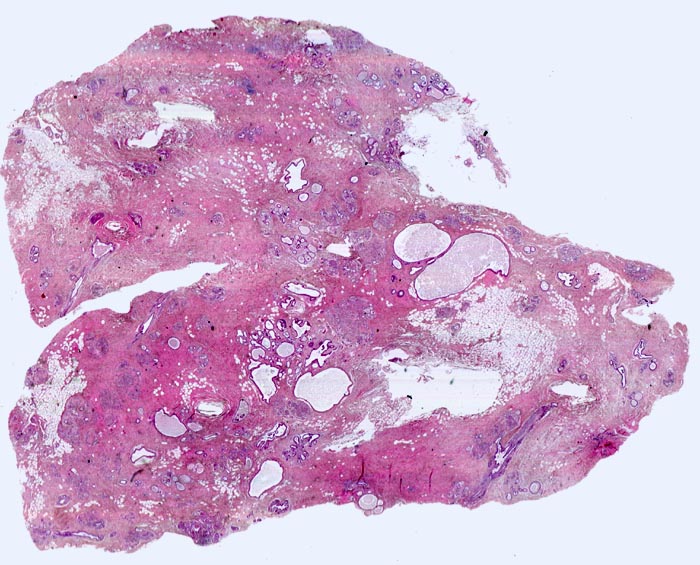

Basel 3BA FS/ Fibrös zystische Mastopathie mit Mikroverkalkungen

Fibrös zystische Mastopathie mit Mikroverkalkungen

Makroskopisch bildet das mastopathisch veränderte Parenchym weisse kompakte fibröse Areale mit Einschluss von Zysten, welche oftmals eingedicktes Sekret enthalten. Neben einer Stromafibrose und zystisch ausgeweiteten Gängen mit Sekretretention findet sich oft eine unterschiedlich ausgeprägte intraduktale Proliferation von luminalen und basalen Epithelzellen. Nicht selten liegen als Begleitbefund kleine Fibroadenome, eine sklerosierende Adenose oder Gänge mit apokriner Metaplasie vor. Oftmals finden sich auch intraduktale Mikroverkalkungen. Die duktale Hyperplasie ist im Gegensatz zur atypischen Hyperplasie und zum Carcinoma in situ charakterisiert durch eine bunte, ungeordnete Proliferation ungleich grosser polygonaler bis spindeliger Zellen mit Ausbildung von schlitzförmigen Hohlräumen oder dünnen epithelialen Brücken. Die euchromatischen Kerne variieren in Grösse, Form und Lagerung. Bei paralleler Lagerung der Kerne entsteht der Eindruck eines Strömens und Fliessens der Zellen. Das duktale Carcinoma in situ ist von gutartigen intraduktalen Epithelproliferationen abzugrenzen aufgrund seiner Monomorphie (> 5185), Hyperchromasie der Zellkerne und starrer geometrischer Muster (runde scharf begrenzte wie ausgestanzte Lumina (> 5184), breite Brücken und Bögen, Mikropapillen). Eine intraduktale Epithelproliferation mit Atypie wird dann diagnostiziert, wenn nur ein Teil der Gänge oder Läppchen die typischen Veränderungen eines Carcinoma in situ zeigt. Die Abgrenzung der atypischen Hyperplasie von der Hyperplasie ohne Atypie erfolgt aufgrund qualitativer Merkmale und die Abgrenzung der Hyperplasie mit Atypie vom Carcinoma in situ aufgrund quantitativer Merkmale.

• Ausgeprägte Fibrose und zystisch erweiterte Gangstrukturen in organoider Anordnung.

• Im Zentrum des Präparates stark erweiterte Gänge mit intraduktalen peripheren Papillomen.